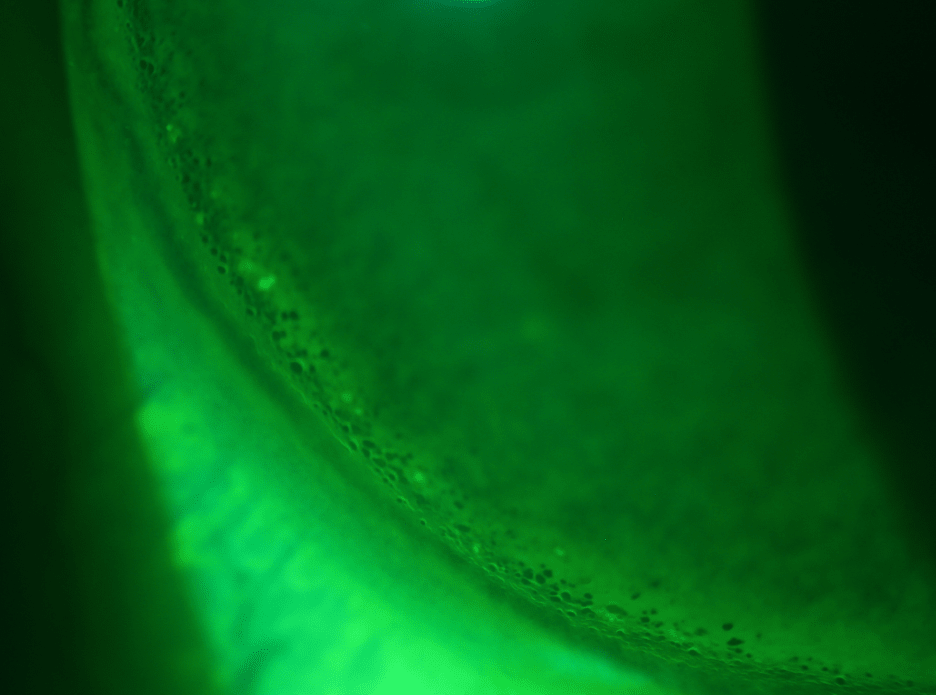

The patient was found to have peripheral corneal epithelial bullae nearly 360º around in both eyes. Evaluation with the scleral lenses on eye demonstrated that the lens was landing on the peripheral cornea just inside the limbus. The rings of bullae therefore are mechanical in nature and not from hypoxia. This is apparent when you observe the contact lens fit with fluorescein (Figure 2).

Mechanical bullae related to scleral lens wear are due to the use of a lens diameter that does not provide a large enough vaulting chamber to allow the lens to land beyond the limbus onto the conjunctival-scleral complex. When a patient’s corneal diameter is at or exceeds the chord diameter of the aspect of the lens designed to vault, the lens will automatically land on the peripheral cornea. Adjustments to the limbal clearance zone of a lens are inadequate, as the intended zone for limbal clearance is inside the point of contact between the lens and the cornea, so limbal clearance adjustments only provide more space inside the point of contact, not over the point of contact.